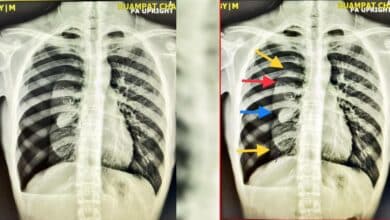

เปิดภาพสยอง เด็ก 16 สูบบุหรี่ไฟฟ้าจัด ปอดแฟบเหลือเป็นก้อน แพทย์เตือน! เลิกได้เลิก

อุทาหรณ์คนติดบุหรี่ไฟฟ้า ใช้เวป (Vape) หรือพอด หรืออีซิกาแร็ตต์ E Cigarett หมอโพสต์เฟซบุ๊กเปิดเผยภาพเอ็กซเรย์ปอด เด็กวัยรุ่น อายุ 16 ปี หายใจแล้วเจ็บหน้าอก รู้ผลแทบช็อก ลมรั่วในช่องปอดขวา แฟบรวมกันเป็